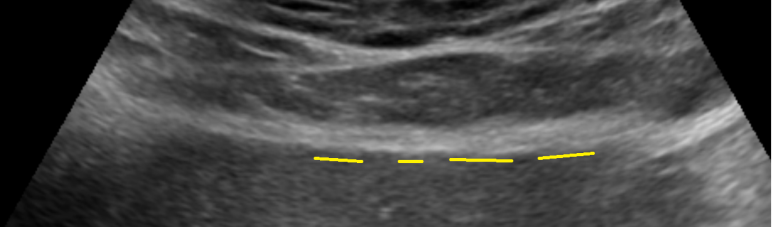

아래와 같이 한컷에서 모래양담석이 있어 보이나 다른 각도에서 재확인 되지 않아 허상?으로 보았으며... 따라서 ; 2023년 초음파에서 담낭오니/모래양 담석이 관찰되지 않아 --> UDCA 중단

이번 초음파에서 아래와 같이 담낭에 소견은 없었는데... --> 과거 미세담석에 준해서 우루사 (이담제) 다시 복용해보기로 결정함